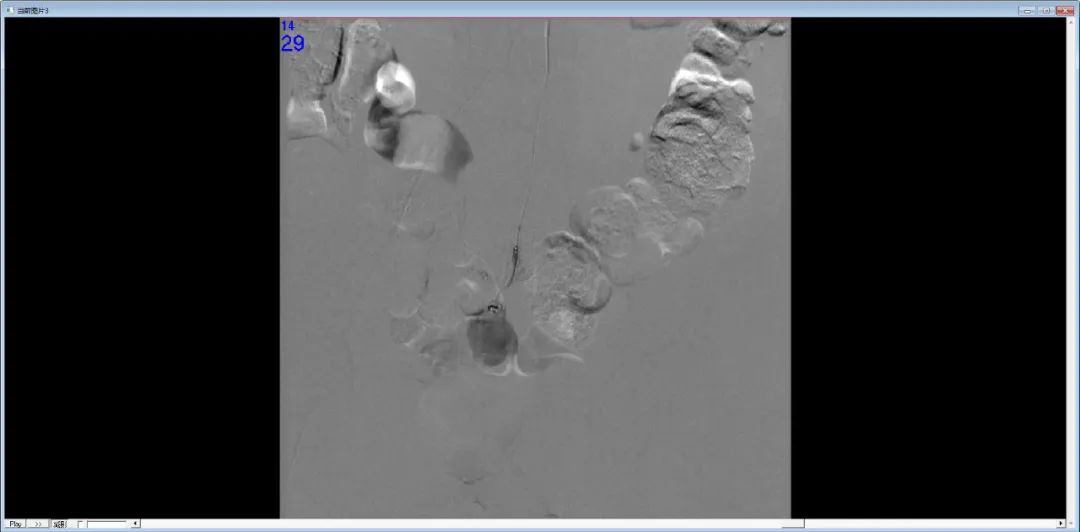

DSA示血管走行中断